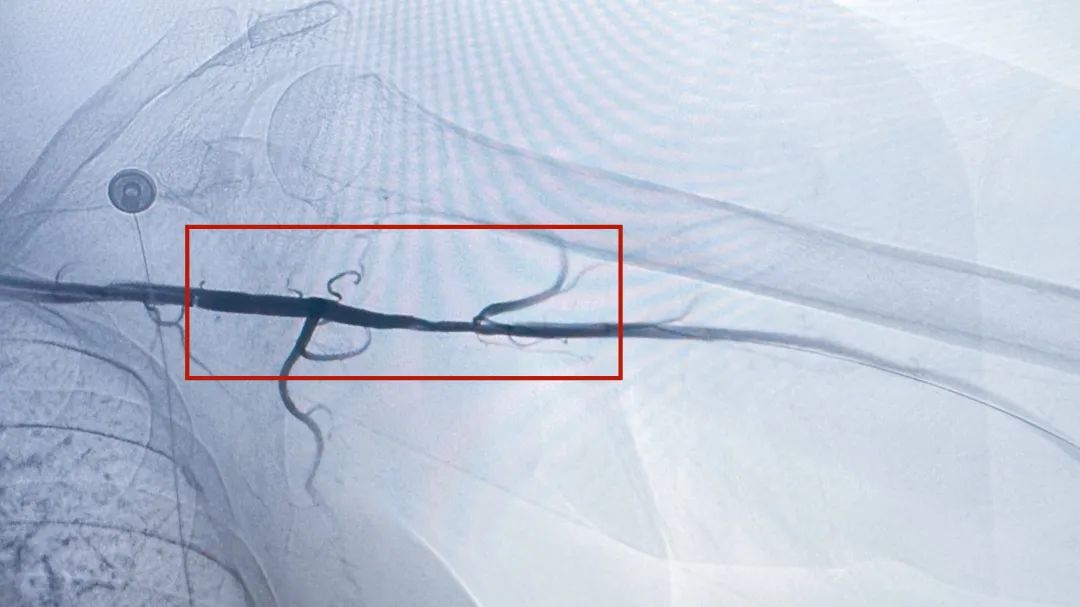

▲介入手术现场

随后,手术团队开始了更为惊险的操作:将直径仅0.3毫米的耐高温导丝穿越完全闭塞的血管段。显示屏上,红色血栓如同狰狞的“血管杀手”,卡在腋动脉的关键位置。“稳住!逐段旋切抽吸!”欧敏富额头沁汗,手中的导丝却稳如磐石。“就像在豆腐里穿针,稍有不慎就会戳破血管。”当机械旋切导管启动时,整个团队屏息凝神——血管内高速旋转的刀头必须精确剥除血栓而不损伤血管内膜,4厘米的血栓被分解成数百块微米级碎屑并安全抽吸。这场持续72分钟的“血管刺绣”,最终以监测仪上消失已久的腋动脉波形重新跃动而画下完美句号。

介入手术过程